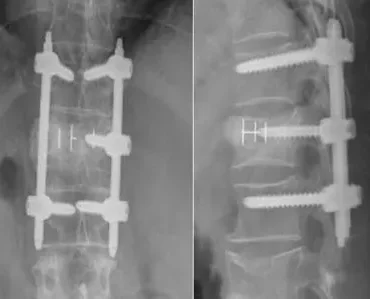

With more than 12 years of experience in neurosurgery, Dr. Muhammad Aqeel Natt has built a reputation for combining advanced surgical precision with genuine empathy. At The Brain and Spine Centre, our mission is simple: to restore health, relieve pain, and give every patient the confidence of personalized, world-class care.

Whether you’re struggling with a spinal condition, a brain tumor, or nerve-related pain, Dr. Natt’s evidence-based approach ensures the safest and most effective treatment options available today.

We manage the full spectrum of neurosurgical conditions—from brain tumors and neurovascular diseases to complex spine disorders and pediatric neurosurgery. Our advanced treatment solutions are tailored to help patients recover and thrive. Learn more about our services below.

Neurosurgical care requires trust and expertise. Patients across Lahore, Sialkot, Narowal particularly and throughout the Punjab generally rely on Dr. Muhammad Aqeel Natt for his innovative, safe, and patient-centered approach. Our center delivers advanced diagnostics, modern minimally invasive surgery, and structured rehabilitation pathways for comprehensive recovery.